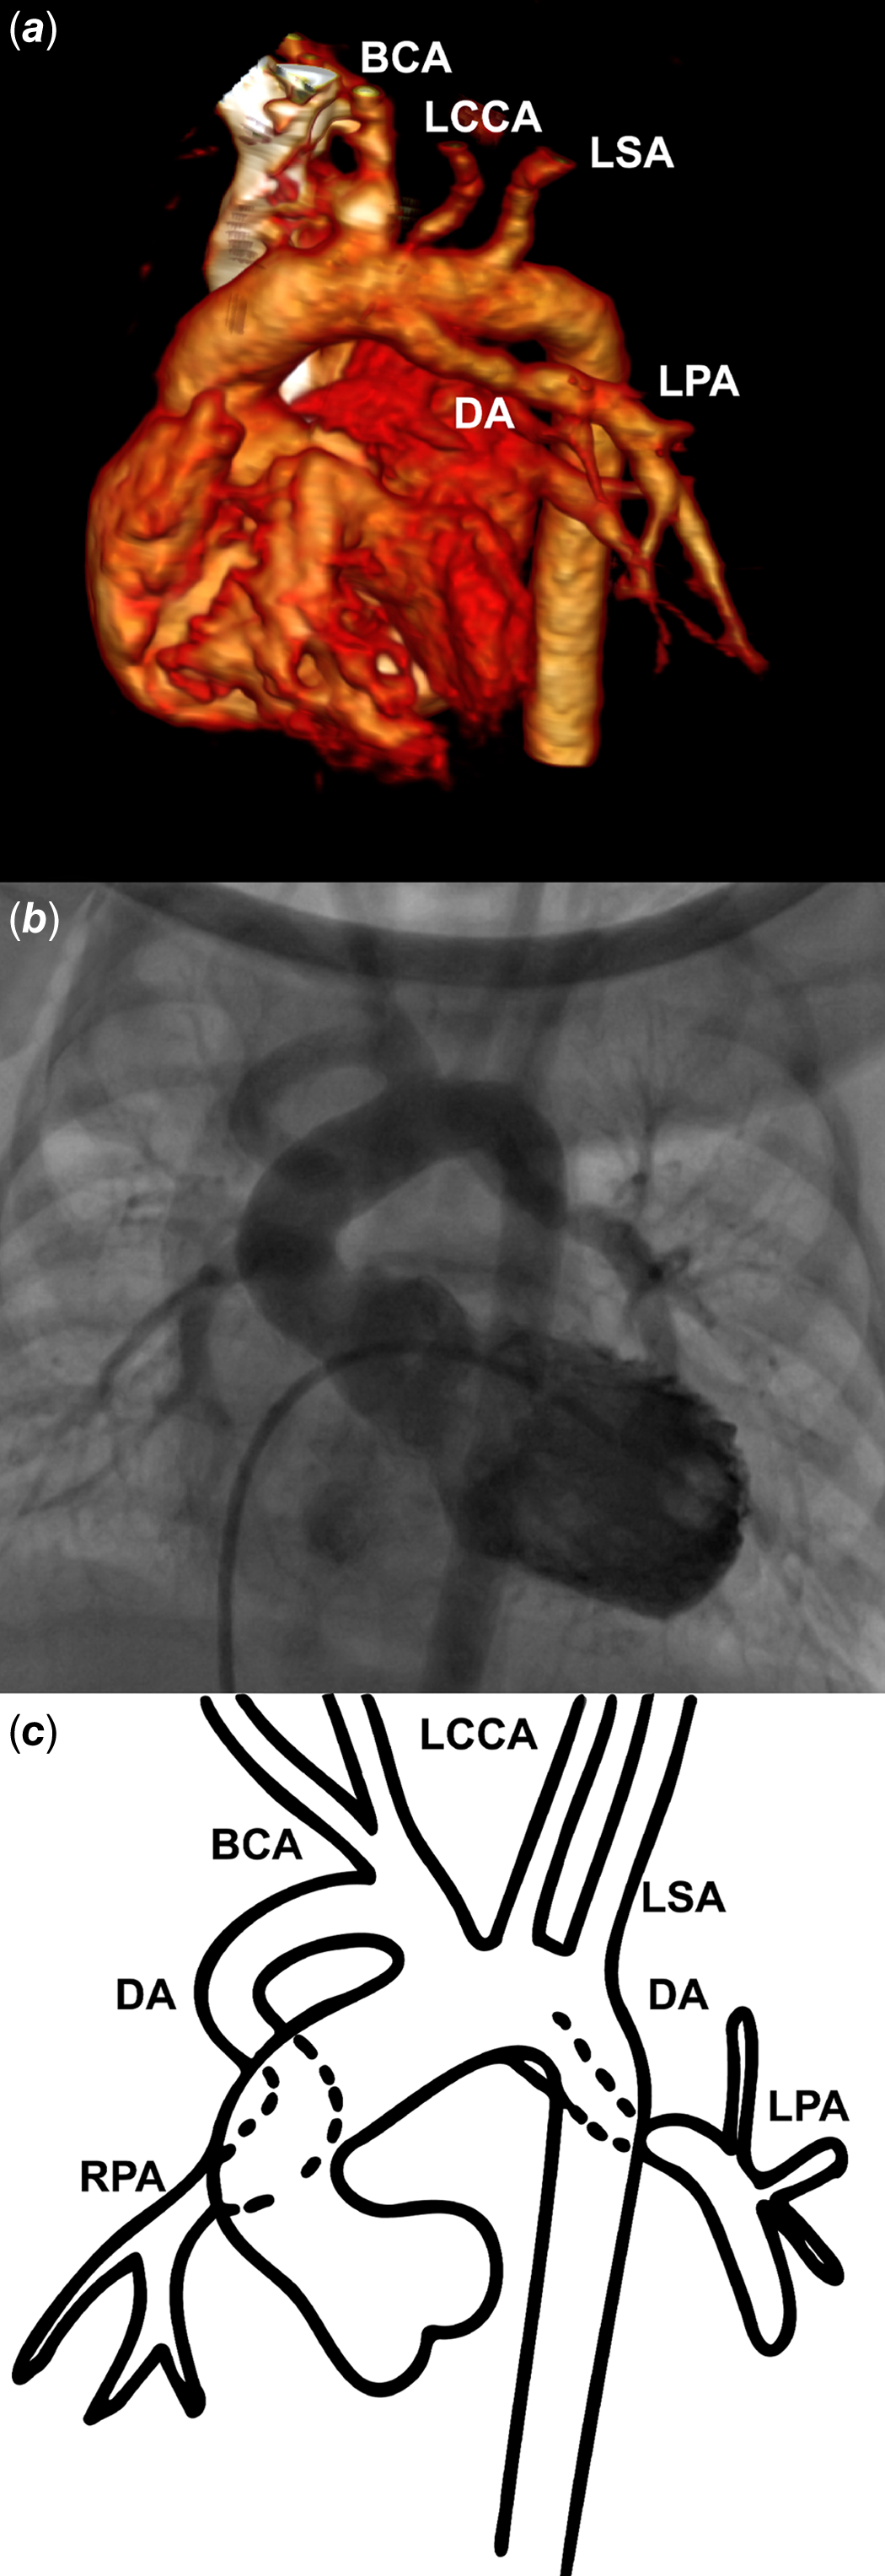

A 2500-gram term newborn was admitted in our department from the delivery room for the management of a prenatally diagnosed tetralogy of Fallot with pulmonary atresia. His peripheral oxygen saturation level was 80% on pulse oximetry in room air. Transthoracic echocardiography showed a normal atrial arrangement and confirmed a tetralogy of Fallot with pulmonary atresia and discontinuous pulmonary artery branches. At day-of-life 1, saturation dropped to 60%. Echocardiogram showed normally supplied right pulmonary artery but a constricted left ductus and functionally closed left pulmonary artery. Prostaglandin (PGE-1, 10 ng/kg/min) infusion was started and allowed restoration of the left pulmonary artery perfusion and subsequent improvement in oxygen saturation. A CT scan was performed to delineate ductal anatomy (Fig 1). After multidisciplinary team discussion, a transcatheter approach was preferred and the baby was transferred to the catheterisation laboratory. The left ventricular angiogram showed that the left pulmonary artery was supplied by a ductus arteriosus arising from the aortic arch, whilst the right pulmonary artery came straight from the brachiocephalic artery (Fig 1). There was no major aorto-pulmonary collateral artery. An elective ductal stenting with a 3.5 × 13 mm bare metal coronary stent was performed on the fifth postnatal day, with a 5-French Judkins Left 3.5 coronary guide catheter advanced through right ventricle into the aortic arch from the right femoral vein (Fig 2). PGE-1 had been stopped 6 hours before ductal stenting to allow the ductus to be well constricted. After ductal stenting, the baby was started on aspirin and clopidogrel. Four days later, oxygen saturation suddenly dropped again, up to 55%. Echocardiogram showed a well-positioned stent on the origin of the left pulmonary artery with an unrestrictive blood flow, but no right pulmonary artery was seen anymore. The patient was sent back to the catheterisation laboratory, where hand contrast injection demonstrated sub-occlusion of the proximal segment of the right pulmonary artery, which was consistent with ductal constriction of a second, right ductus arteriosus supplying the right pulmonary artery. Emergent ductal stenting of the right ductus was performed using a 3.5 × 24 mm bare metal coronary stent with a 5-French Judkins Right 3.0 coronary guide catheter into the brachiocephalic artery from the right femoral artery (Fig 2). This allowed clinical improvement and saturation increase up to 88%. Both stenting were uneventful, and the patient remained on aspirin and clopidogrel till surgical repair with pulmonary artery reimplantation 10 months later.

Figure 1. Multimodality imaging of bilateral arterial duct. Three-dimensional volume-rendering CT scan ( a ), left ventricular angiography ( b ), and a picture ( c ) showing bilateral ductus arteriosus feeding discontinuous pulmonary arteries. The left pulmonary artery is supplied by a left ductus arteriosus arising from the aortic arch. The right pulmonary artery is supplied by a right ductus arteriosus coming from the brachiocephalic trunk. RPA = right pulmonary artery; DA = ductus arteriosus; BCA = brachiocephalic artery; LCCA = left common carotid artery; LSA = left subclavian artery; LPA = left pulmonary artery.